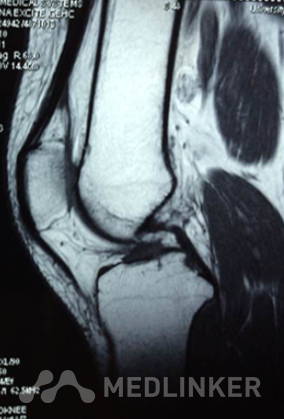

查体:左下肢无畸形,左膝关节无静脉曲张、肿胀等,皮温正常,关节间隙压痛,麦氏征(+),蹲走试 验(-),过伸试验(-),过屈试验(-),浮髌征(-),髌骨加压研磨试验(+),前抽屉试验(+) ,后抽屉试验(-),侧方应力试验(-),lachman征(+),关节活动度0-135度,股四头肌无明显萎缩 ,肌力正常;肢端血运、感觉、活动正常。双上肢及右下肢其余关节未见明显异常。 X线提示:左膝关节退行性变。 MR提示:左膝关节前交叉韧带内侧束损伤。

诊断 左膝关节前交叉韧带前内侧束断裂行左膝关节镜检,前交叉韧带分束重建术